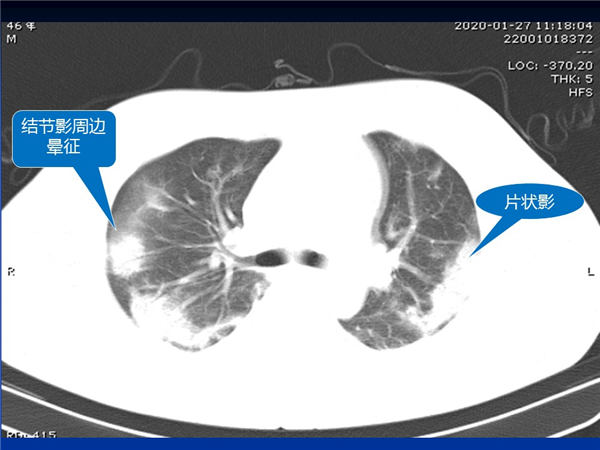

【病例分享】新型冠狀病毒感染肺部CT影像4例(常德市第一人民醫(yī)院)

幻燈片7.jpg